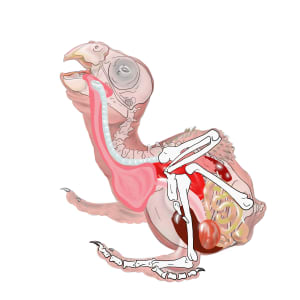

- Nestling Parrot Anatomy

Reference material for care-givers and veterinary staff at wild parrot rescue, rehab and release facilities

- Subject Matter: Anatomy series of nestling parrot